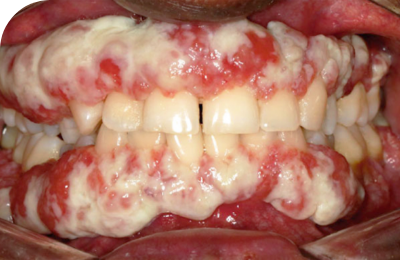

Ligneous gingivitis with gum swelling and lesions

Ligneous gingivitis in a real patient with PLGD-14

32% of people with PLGD-1 experience gingival involvement6†

Ligneous gingivitis is typically painless but can lead to periodontal destruction (tissue loss) and ultimately tooth loss if left untreated.3

Ligneous gingivitis caused by congenital plasminogen deficiency type 1, manifesting as gum lesions Respiratory tract lesions in plasminogen deficiency type 1 patient Skin lesions on arm

Real patients with PLGD-14,11

Lesions due to PLGD-1 may present in a variety of ways, from watery, stringy pseudomembranes to thick wood-like lesions.3

Not only does symptom severity fluctuate over time, but the overall severity of the disorder varies greatly from patient to patient depending on the location and duration of lesions. Internal lesions can even occur without clinical suspicion.3,5

Even members of the same family impacted by PLGD-1 can present with drastically different manifestations.3